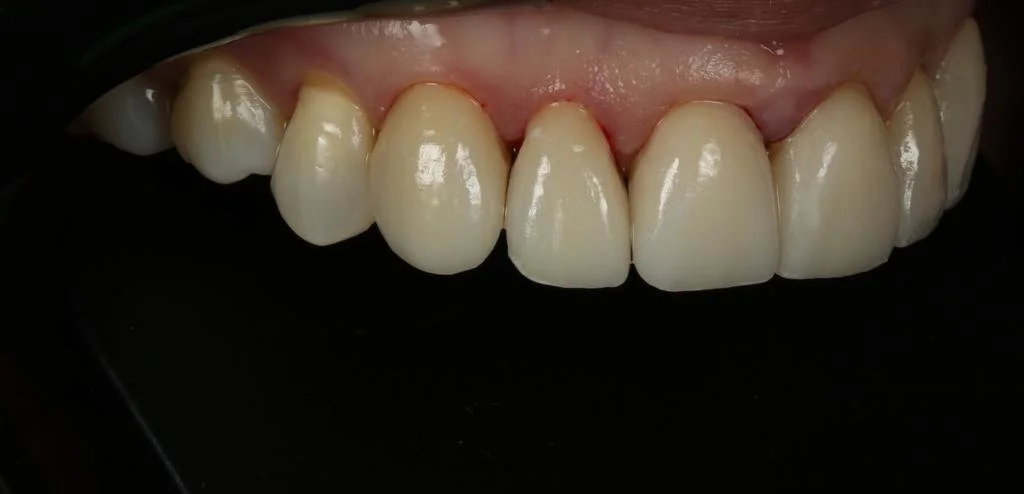

Cerec Reshape and Stain Graze